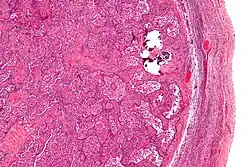

Gonadoblastomas are precancerous lesions that predominantly form in intersex people with gonadal dysgenesis and a Y chromosome.[42][43] This includes conditions such as Swyer syndrome or Turner syndrome with Y chromosome mosaicism.[44][42] These cancer risks are addressed using genetic screening and performing a gonadectomy if necessary.[42]

Micrograph of gonadoblastoma

Image of gonadoblastoma at low magnification